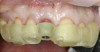

(13.) Postoperative image of site No. 8 taken 4 months after extraction and grafting.

Figure 13